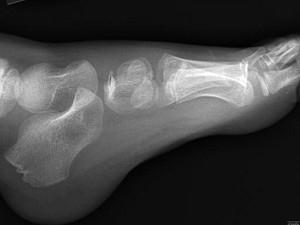

问题 男,5岁,足背肿痛,请结合图像,选出最可能的诊断 ( )

选项 A、软骨发育不全 B、剥脱性骨软骨炎 C、跗舟骨骨折 D、成骨不全 E、跗舟骨缺血坏死

答案 E